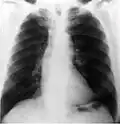

Radiografía

En este segmento de las imágenes médicas se puede encontrar desde los más simples exámenes de rayos X hasta estudios complejos como el sistema digestivo. Las imágenes son obtenidas gracias a las diferentes capacidades que poseen los tejidos de atenuar las radiaciones X, han sido utilizados en el ámbito médico desde su descubrimiento en 1895 por Wilhelm Conrad Röntgen y hasta nuestros días son ampliamente utilizados para realizar diagnósticos diferenciales en el área de la traumatología (pesquisa de fracturas, alteraciones de los huesos y malformaciones), a la vez permiten visualizar algunos órganos de menor densidad como los pulmones, en cuyo caso es posible detectar diferentes patologías que afectan a este órgano cono es el caso de la acumulación de polvos que al ser inhalados causan enfermedades definidas como silicosis. Todo estudio radiográfico está compuesto, a lo menos, por dos proyecciones lo que permite visualizar la estructura estudiada en dos planos perpendiculares.

Este método de adquisición de imágenes puede ser asociado con el uso de medios de contrastes, hidrosolubles sobre la base de bario o yodo dependiendo de la vía de administración, los que permiten realizar estudios específicos del sistema digestivo, urinario lo cual facilita el diagnóstico de una gran variedad de patologías. Desde su descubrimiento hasta la actualidad son muchas las transformaciones que han afectado a los equipos utilizados para tomar radiografías, todas ellas tendientes a reducir de manera considerable la exposición a radiaciones ionizantes tanto de los profesionales (médicos y tecnólogos médicos) que obtienen las imágenes, como la irradiación a la cual está expuesto el paciente. En los últimos años, con la llegada de los equipos digitales, las dosis de radiación utilizadas para obtener un mismo examen se han reducido de manera considerable (la primera radiografía de una mano que se obtuvo demoró casi 15 minutos de exposición, hoy el mismo examen puede ser adquirido con apenas 20 a 30 milisegundos de exposición) lo que puede implicar una reducción de dosis considerable que podría llegar a ser más de 1000 veces menor.

-

Radiografía convencional -

Tomografía convencional -

Tomografía axial computarizada